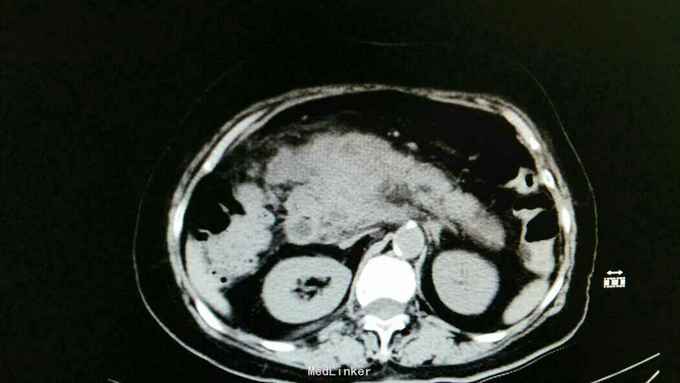

胰头肿块型胰腺炎1例

间断性腹痛不适9个月,加重7天。 患者9个月来进食后出现腹痛不适,以中上腹为著,呈间断性胀痛。以“胃病"于当地诊所治疗。近7天来以上症状加重,伴发热,最高达38.5摄氏度。门诊查彩超:胆囊泥沙结石伴胆囊炎,急性胰腺炎。收入院。

右上腹轻压痛,中上腹压痛,可触及一肿块,约6cm大小,边界尚清。 血淀粉酶不高。

胰头肿块型胰腺炎 胆囊结石伴胆囊炎 给子抑酸,抑酶,抗炎,对症及支持治疗。

现患者复查CT:较之前明显好转。 讨论:本病例强调问诊时"急性胰腺炎”反复发作史,而本次发病则为慢性胰腺炎急性发作。病因则考虑为胆源性。